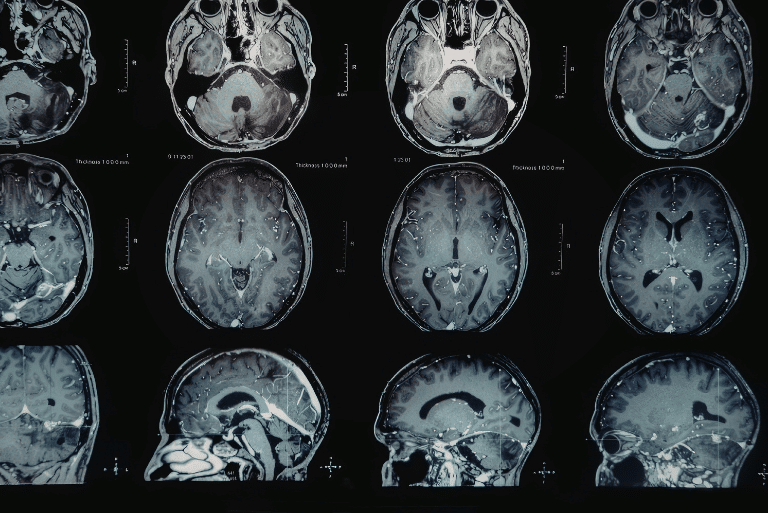

Как се определя какъв вид е появилия се тумор (доброкачествен или злокачествен тумор)? Проф. Кьос...